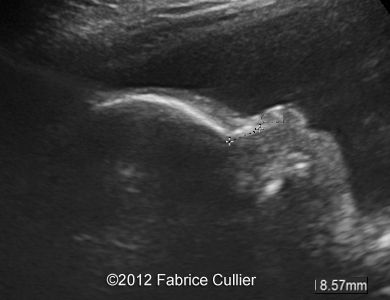

Image 6, 7 : 2D sagital views of the face at 29 weeks shows retrognatism with normal nose bones.

5

6